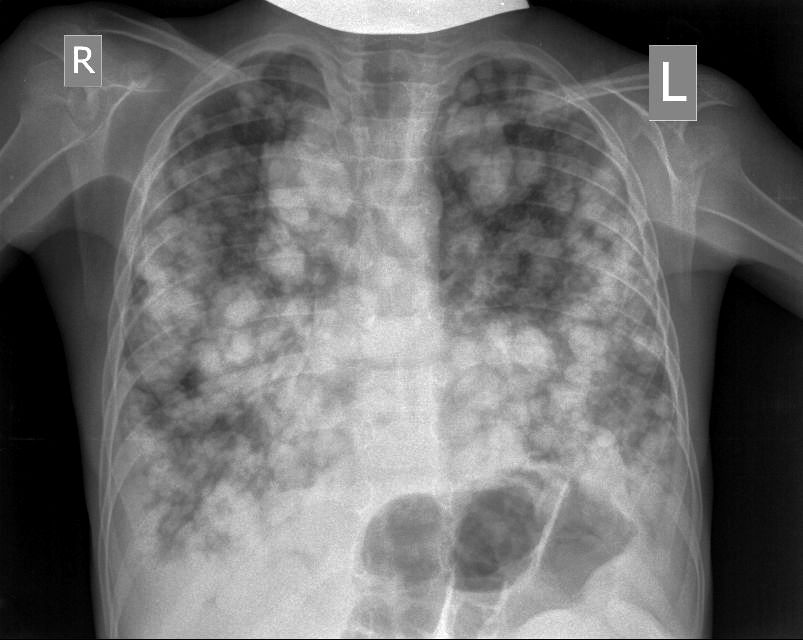

И в довершение - рентгенограмма лёгких для верификации ультразвуковых изображений. Я думал, что такое бывает только в старых книгах

ЦДК образований в лёгких не делал, если быть откровенным, порядок находок у этого пациента был следующим: МТС в печени - изменения в нижней доле правого лёгкого - забрюшиное пространство - левая почка - левое лёгкое - правое лёгкое - рентген лёгких. Картина в комплексе была и так ясна, т.е. то, что это MTS сомнений не вызывало. Ну а после патогномоничной рентгеновской картины - вопросов тем более не было.

Пришло извещение на онкозапущенность по данному случаю. Верифицирована нефробластома, ребёнок проходит химиотерапию. Только что состоялось заседание комиссии по онкозапущенности, комиссия пришла к выводу, что нужно решать вопрос об УЗИ - скрининге брюшной полости у детей.